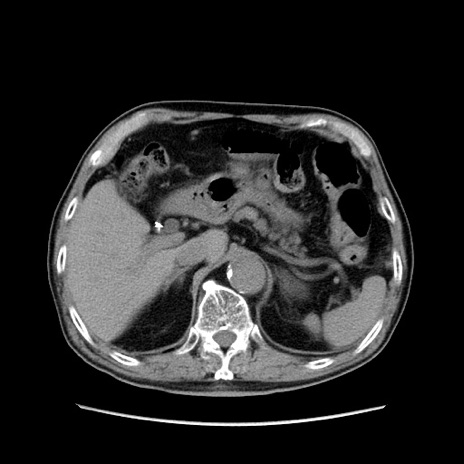

症例24(横断像)

【症例】80歳代男性

【主訴】左側腹部痛、嘔吐

【現病歴】本日早朝より左腹部に痛みあり。昼頃嘔吐認めたため、救急要請。

【既往歴】直腸癌(Mile手術)、胆摘

【身体所見】意識清明、BT 35.9℃、BP 221/93mmHg、SpO2 97%(RA) 、腹部:左ストーマ周囲に限局性の腹部膨隆あり。 膨隆部自発痛・圧痛あり・軟。

【データ】WBC 7700、CRP 0.09